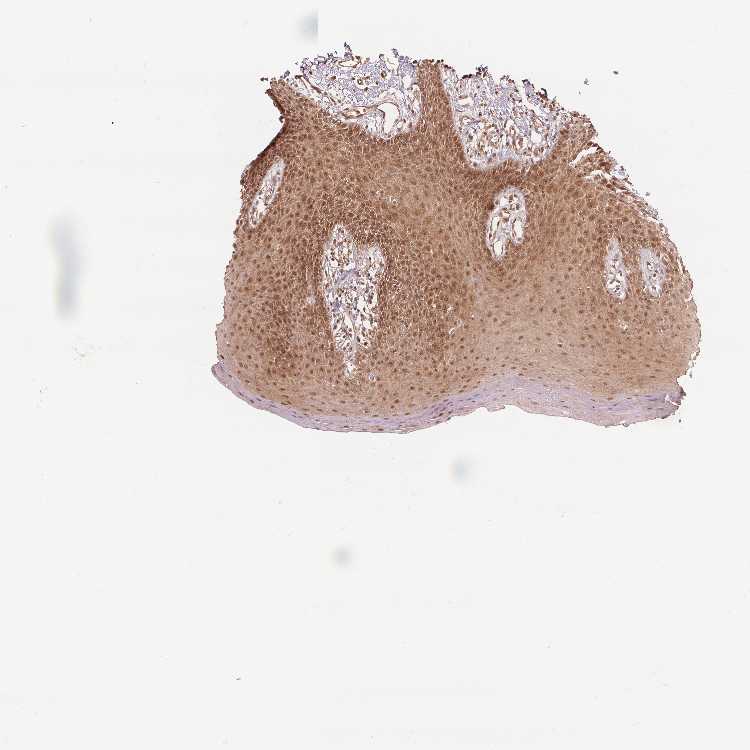

TISSUE PRIMARY DATA ORAL MUCOSA Show tissue menu

ORAL MUCOSA - Antibody stainingi

Antibody staining in the annotated cell types in the current human tissue is reported as not detected, low, medium, or high, based on conventional immunohistochemistry profiling in selected tissues. This score is based on the combination of the staining intensity and fraction of stained cells.

Each image is clickable and will lead to virtual microscopy that enables deeper exploration of all samples and also displays staining intensity scores, fraction scores and subcellular localization as well as patient and tissue information for each sample.

Antibody HPA065425Antibody CAB069426

Squamous epithelial cells MediumMedium